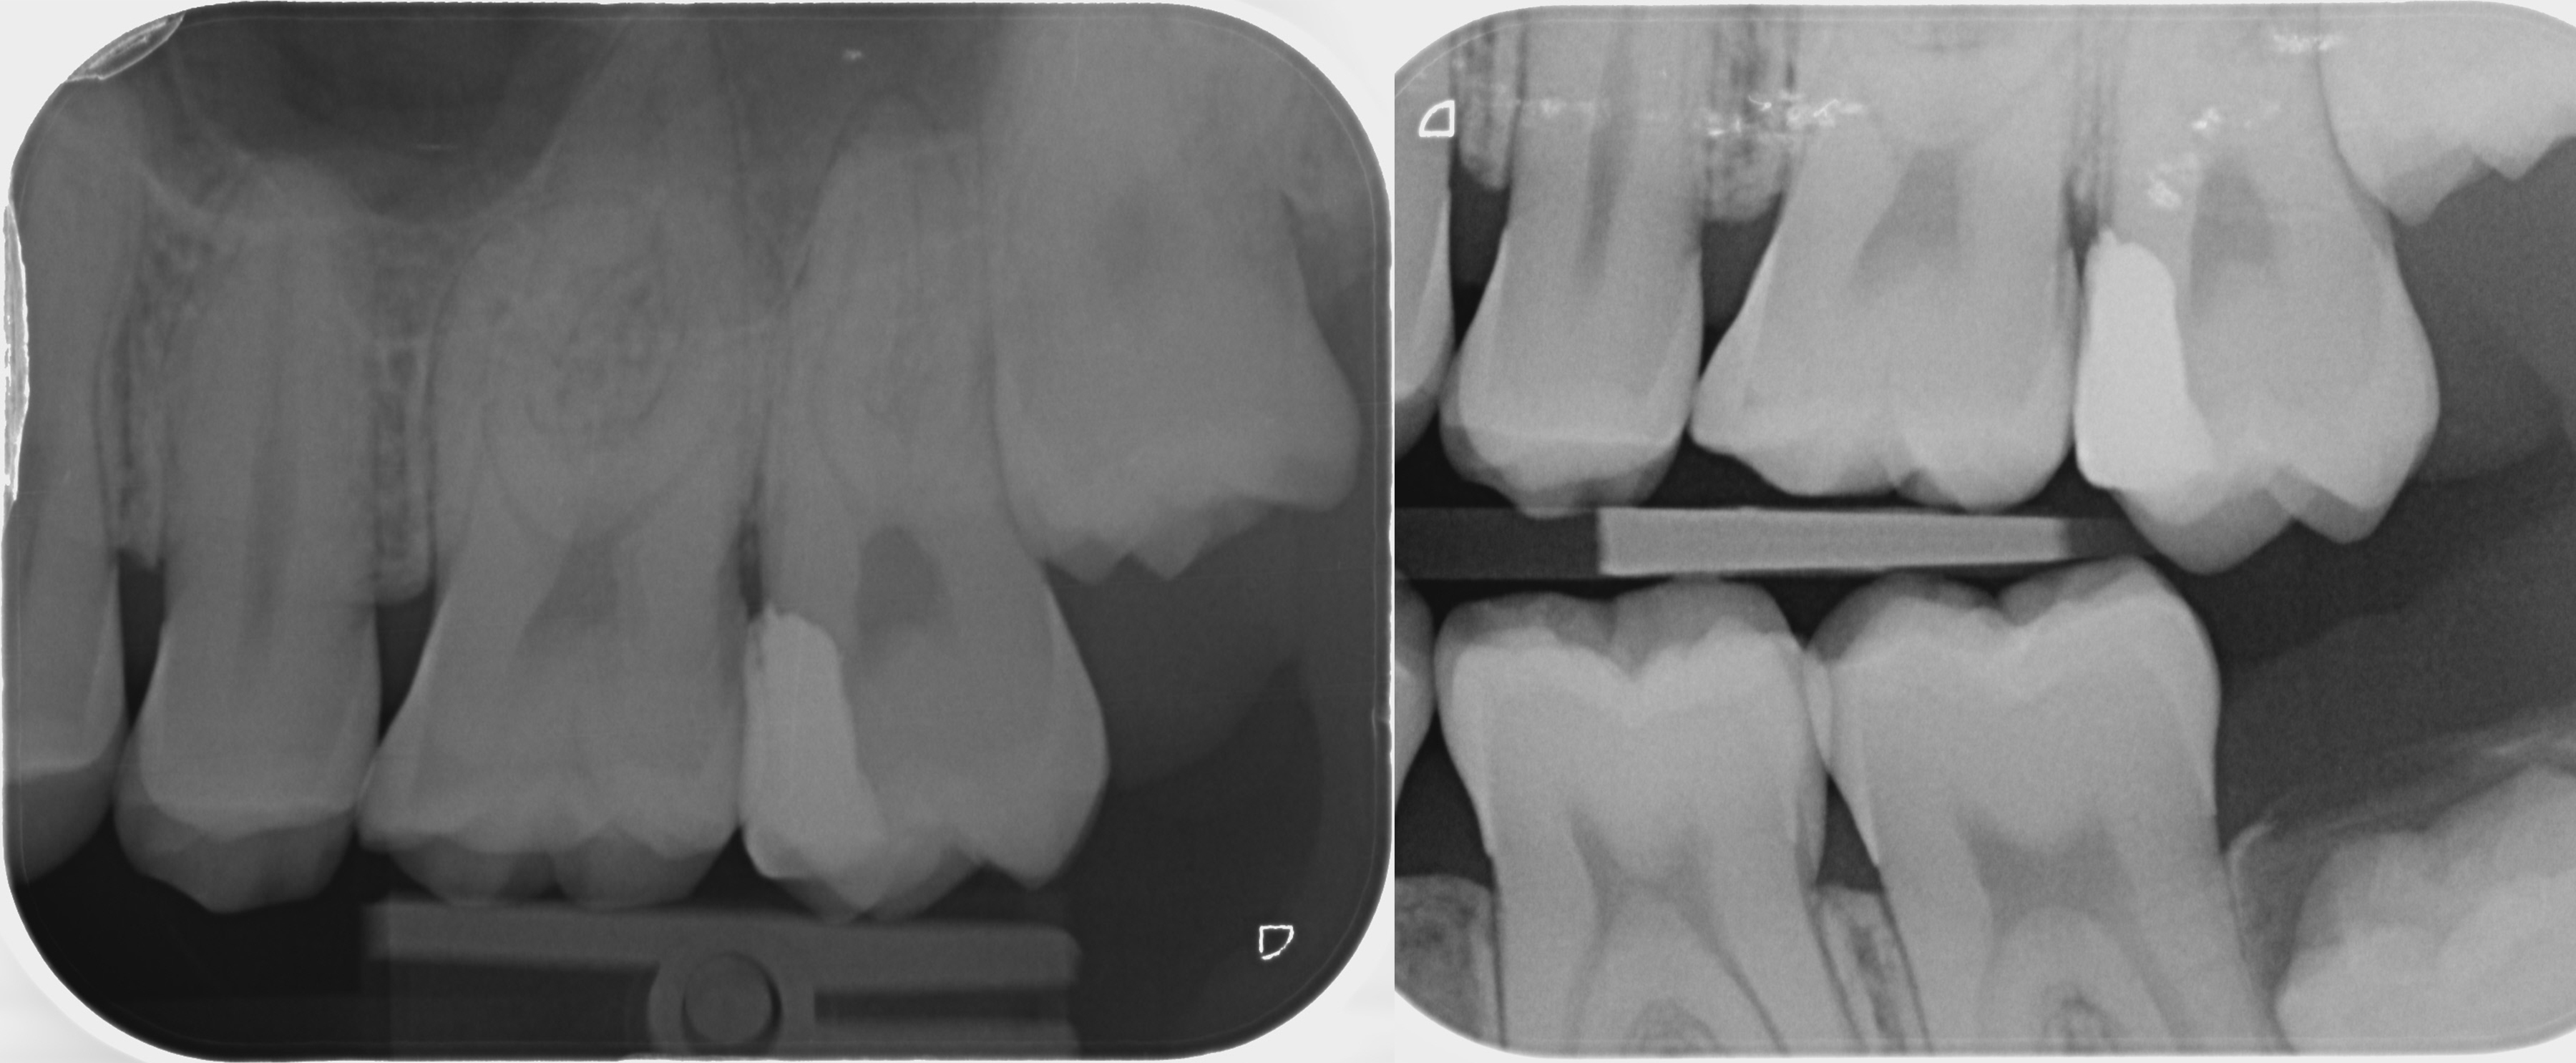

Recentelijk ben ik naar de tandarts geweest voor misschien wel mijn laatste controle bij mijn huidige tandarts, omdat ik naar het buitenland zal verhuizen voor onbepaalde tijd. Bij de controle zijn voor de zekerheid nog foto's gemaakt en constateerde de tandarts een ontsteking van mijn kies waar al eerder een vulling in was geplaatst (linker foto). Ik heb wel eens sporadisch last van deze kies, maar heb eigenlijk verder nooit kiespijn. Hij zei dat er een zwart randje te zien was op de foto. Klopt dat? Ik vind het erg lastig te zien op de foto.

Hij raadde een wortelkanaalbehandeling aan. Ik vroeg of extractie ook geen mogelijkheid is aangezien de kies toch weinig tot geen functie heeft bij het kauwen (rechter foto). Op deze manier zou er een kans kunnen zijn dat de verstandskies (nu nog onder het tandvlees) de plaats inneemt van de huidige ontstoken kies. Als deze niet neerdaalt lijkt me dat geen ramp, omdat de huidige kies dus ook geen functie heeft. De tandarts zei dat ik zelf de keuze mag maken en heb gekozen voor de extractie die binnenkort zal worden uitgevoerd.

Recentelijk ben ik naar de tandarts geweest voor misschien wel mijn laatste controle bij mijn huidige tandarts, omdat ik naar het buitenland zal verhuizen voor onbepaalde tijd. Bij de controle zijn voor de zekerheid nog foto's gemaakt en constateerde de tandarts een ontsteking van mijn kies waar al eerder een vulling in was geplaatst (linker foto). Ik heb wel eens sporadisch last van deze kies, maar heb eigenlijk verder nooit kiespijn. Hij zei dat er een zwart randje te zien was op de foto. Klopt dat? Ik vind het erg lastig te zien op de foto.

Hij raadde een wortelkanaalbehandeling aan. Ik vroeg of extractie ook geen mogelijkheid is aangezien de kies toch weinig tot geen functie heeft bij het kauwen (rechter foto). Op deze manier zou er een kans kunnen zijn dat de verstandskies (nu nog onder het tandvlees) de plaats inneemt van de huidige ontstoken kies. Als deze niet neerdaalt lijkt me dat geen ramp, omdat de huidige kies dus ook geen functie heeft. De tandarts zei dat ik zelf de keuze mag maken en heb gekozen voor de extractie die binnenkort zal worden uitgevoerd.